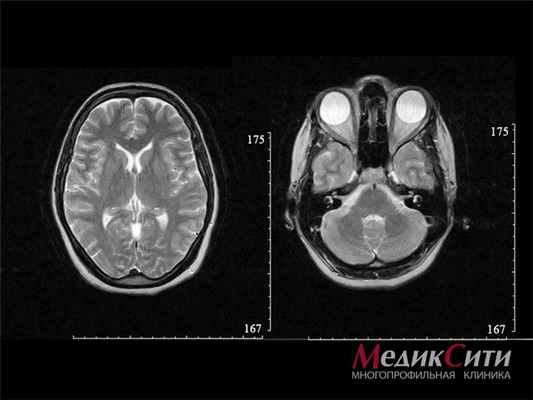

МРТ головного мозга